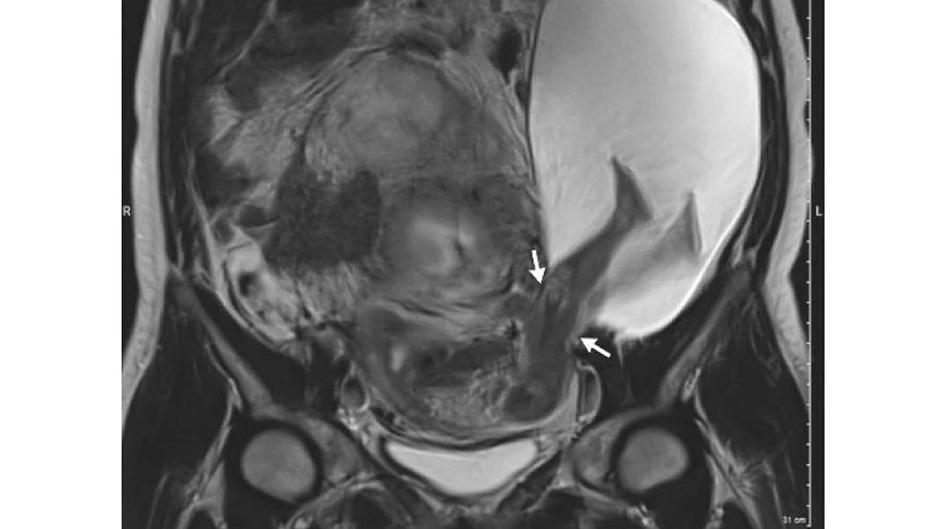

Kako se navodi, fetus je uspio progurati dio tijela proz maternicu svoje majke, i tako živi djelomično dodirujući njene unutarnje organe. Ono što je divno u cijeloj priči - svi su zdravi i živi.

Majka stara 33 godine otišla je na rutinski pregled kada su doktori na snimci otkrili ovu rijetku pojavu. Medicinsko osoblje u Sveučilišnoj bolnici u Francuskoj kažu da nikada nisu vidjeli ovakav slučaj.

Doktori kažu da je pacijentica imala već pet carskih rezova tako da je moguće da su ožiljci na maternici mogući uzrok toga da se ona rascijepala.